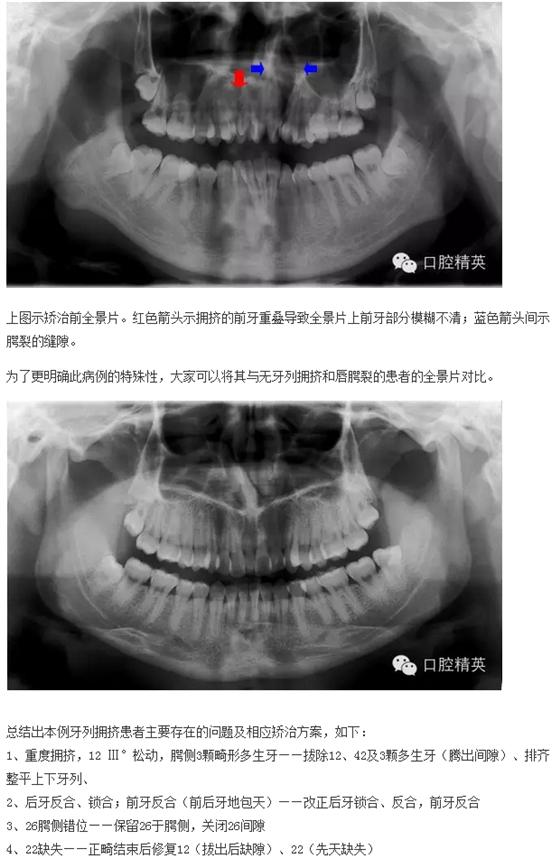

下面來個圖,震撼一下大家的心靈。